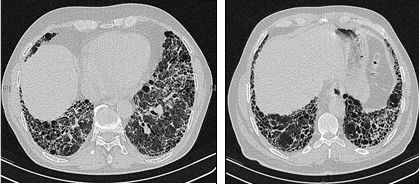

Fibrosis on lung CT shows subpleural patches, which progress to diffuse fibrosis and eventually forms a ‘honeycomb’ pattern which is an indicator of end-stage pulmonary fibrosis.